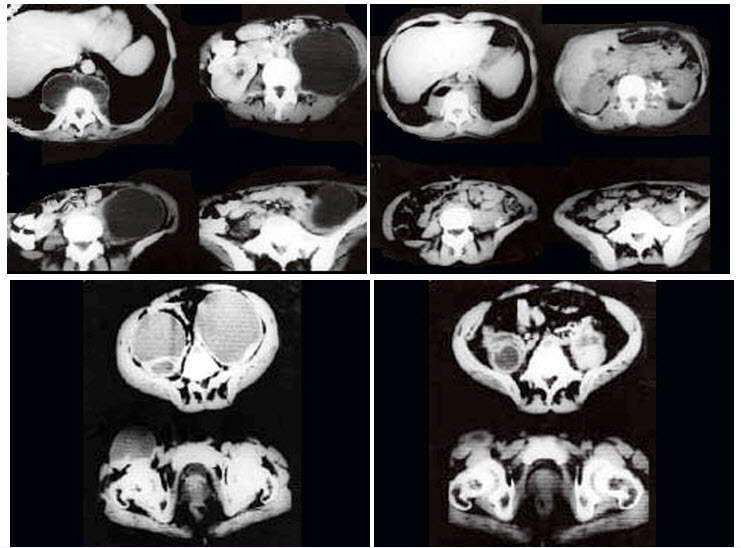

女,34岁,咳嗽,腰背疼痛二年,CT检查如图,最可能的诊断是()

A、结核性脓肿

B、囊肿

C、淋巴管瘤

D、卵巢囊肿

E、卵巢囊腺瘤

正确答案:

A